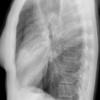

Case 2 Lingular pneum PA

Date: 04/17/2005

Views: 6019